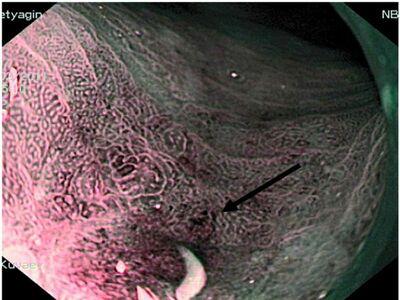

Метаплазия — аномальный этап, приводящий к переформированию одного вида тканей в другой, сопровождающийся отличительными чертами функционального и морфологического плана.

Метаплазия — аномальный этап, приводящий к переформированию одного вида тканей в другой, сопровождающийся отличительными чертами функционального и морфологического плана. На данный момент, ученые выделили следующие разновидности недуга:

- Железистая — локализация поражения происходит в желудочковом, кишечном и пищеводном отделе. Подобный процесс, начинающийся в пищеводе, фиксируется в случаях предопухолевых процессах или воспалениях.

- Плоскоклеточная — протекает с заменой однослойного, призматического или цилиндрического участка эпителия на многослойный. В результате может наступить ороговение. Обычно, представленный тип болезни поражает слизистые районы организма.